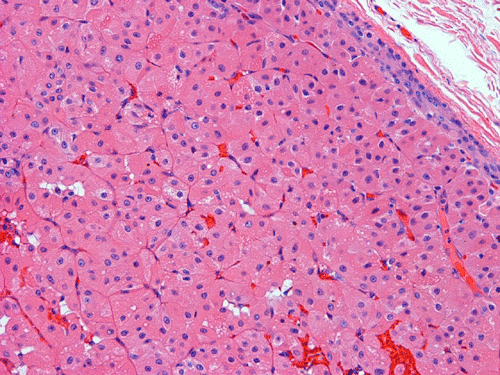

Pathology of the Case: Grossly, the tumor was a small 1 x 2 cm well demarcated nodule embedded within the mid portion of the salivary gland. There is no true capsule (Panel A). The tumor cells arrange in solid sheets and without specific pattern formation (Panel B and C). There is no collagenous tissue within the tumor. The tumor cells are polygonal and rather homogeneous in size. They have low-grade, centrally located nuclei (Panel D), finely granular and distinctly eosinophilic cytoplasm. The granular feature is best appreciated in the cytoplasmic preparation that is prepared while the tumor is being examined before fixation (Panel E).  There is no necrosis or mitotic figures.

Microscopically, oncocytes have a very characteristic appearance with granular eosinophilic cytoplasm due to marked increase in the number of mitochondria mitochondria, pleomorphism of mitochondria, and a paucity of other organelles. The tumor cells have little variation among different tumors or different part of the same tumor. Characteristically, the tumor cells are rather uniform and polygonal in shape. The cytoplasmic membrane can be readily recognized. The nuclei are usually round, centrally located, and nucleoli are present. The cells are arranged in uniform solid sheets without a specific pattern  or they may aggregate into clusters, and sometimes they form duct-like structures. Thin fibrovascular septa are present. Oncocytomas may have a clear cell component secondary to accumulation of cytoplasmic glycogen 6. A PAS stain with and without diastase digestion will be very helpful in recognizing the glycogen. High grade nuclear atypia is only seen exceptionally. Phosphotungstic acid hematoxylin (PTAH) is a good stain that would stain the mitochondria dark. However, the stain is rarely called to service for this purpose as the cytoplasm is typically characteristic enough for recognition without special stain. In clear cell variants, however, PTAH may help. Mitotic figures are not readily seen. In most situations, the diagnosis of oncocytoma is not a particularly challenging one.